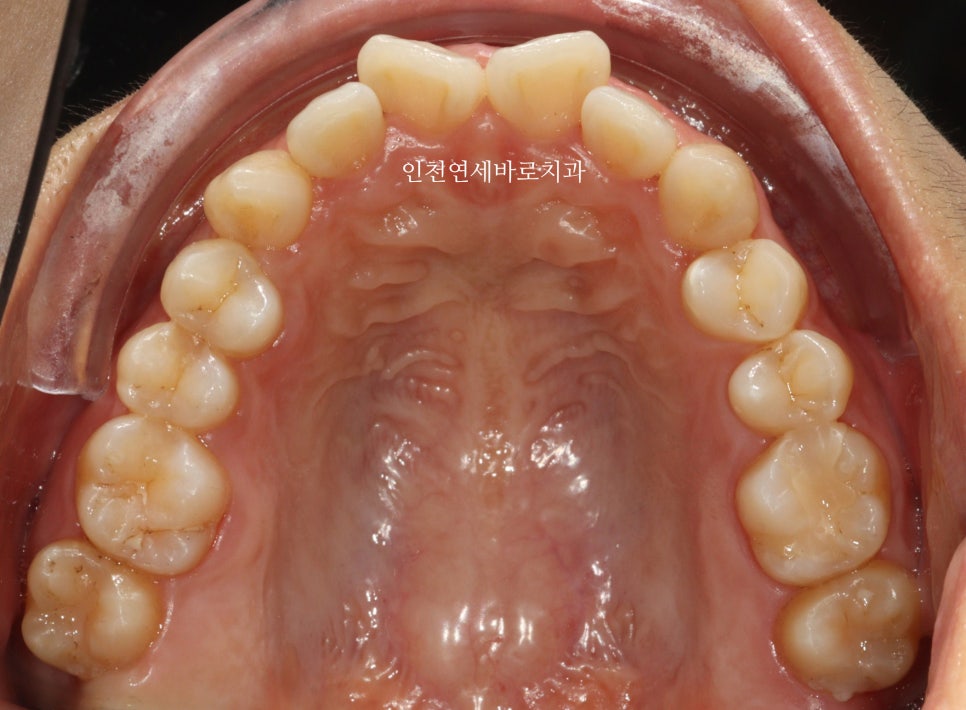

2024년 6-7월 – 치료 중간 단계

시작 후 약 4-5달 후 사진입니다.

이 환자분은 14개의 장치가 끝난 후 한번의 재제작을 했습니다

위 사진이 7월에 재제작 했을 때 모습입니다.